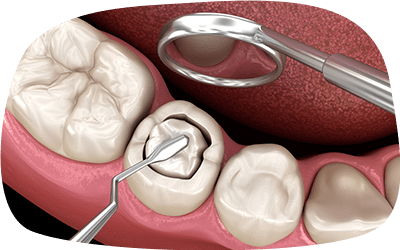

治療プロセス

-

歯髄または過去に

充填した薬剤の除去感染した神経や組織または、

過去に処置した際に充填した薬剤を除去します。 -

根管の洗浄と消毒

根管内部を徹底的に清掃し、消毒します。

根管充填

無菌状態を維持するために薬剤で根管を密閉します。